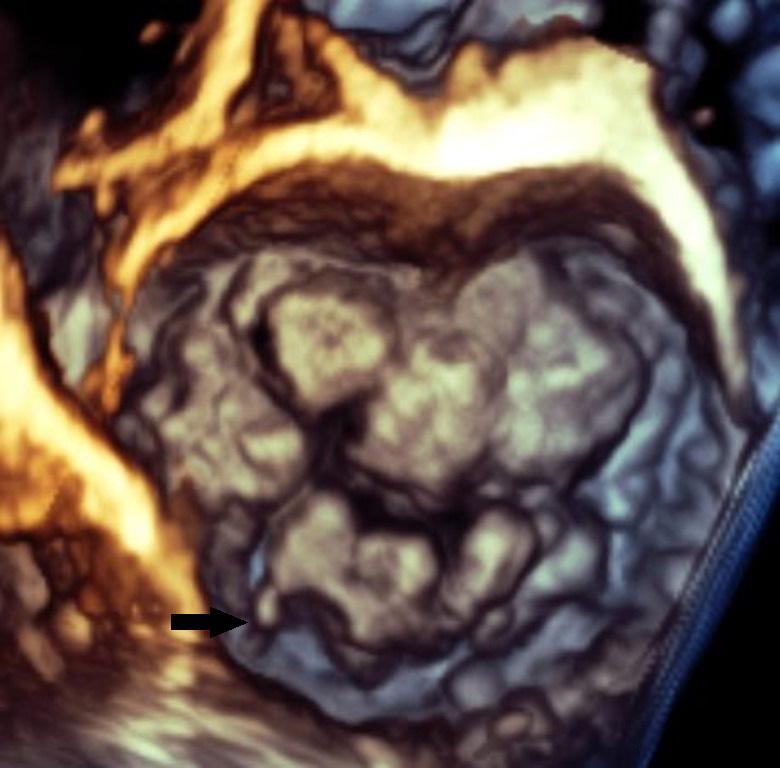

Arrhythmogenic Mitral Valve Prolapse

Theofanis George Korovesis, Paraskevi Koutrolou-Sotiropoulou and Demosthenes George Katritsis https://doi.org/10.15420/aer.2021.28